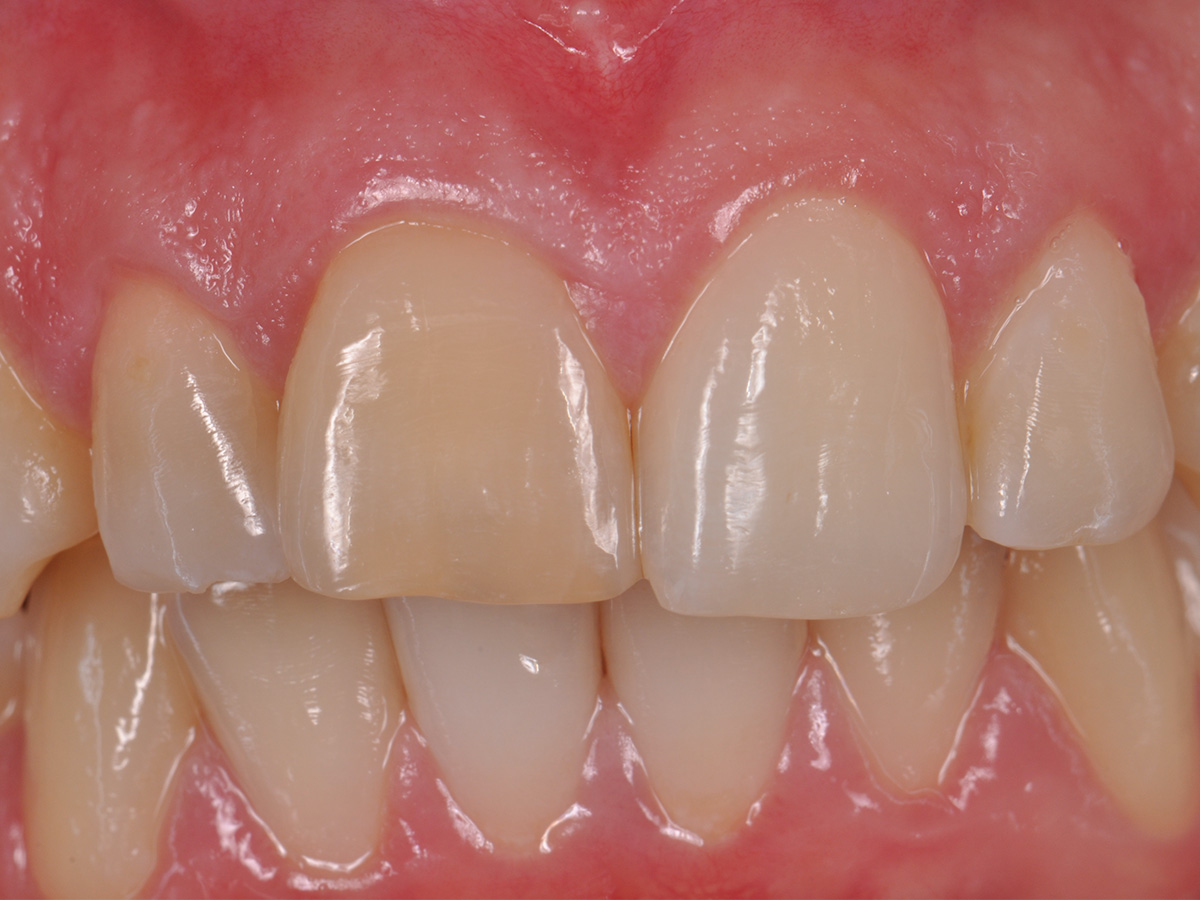

Abbildung 2

Prä-OP: Front nah en face.

Der postoperative Heilungsverlauf zeigte sich unauffällig. Die Nähte wurden am fünften postoperativen Tag bei reizlosen Wundverhältnissen entfernt. Die pathologische Zystenbalgbeurteilung bestätigte den klinischen Verdacht einer radikulären Zyste. Der Befund wurde nach drei, sechs und zwölf Monaten kontrolliert. Nach drei Monaten konnte keine Lockerung der Frontzähne mehr festgestellt werden. Die Narben zeigten sich blande, ästhetisch unauffällig und trotz der hohen Lachlinie gut unter der Oberlippe verborgen (Abb. 16). Die ossäre Durchbauung des gesamten Zystenbereichs erschien bei der radiologischen Verlaufskontrolle nach einem Jahr vollständig und solide (Abb. 17). Ein Zystenrezidiv konnte bislang klinisch und radiologisch ausgeschlossen werden. Sollten im weiteren Verlauf Zahn 11 und/oder Zahn 12 dennoch erneut Probleme entwickeln und entfernt werden müssen, besteht aufgrund er optimalen ossären Rekonstruktion die Möglichkeit, wiederum ohne die Weichgewebearchitektur zu stören, ein Sofortimplantat mit Sofortbelastung zu setzen und damit die soziale Ausfallzeit für die Patientin auf ein Minimum zu reduzieren. Bei stabilen Verhältnissen nach Operation wurde im Verlauf auf Wunsch der Patientin durch den weiter betreuenden Zahnarzt eine Veneer-Versorgung der Oberkieferfront zur vollständigen Wiederherstellung der ursprünglichen Zahnästhetik geplant.